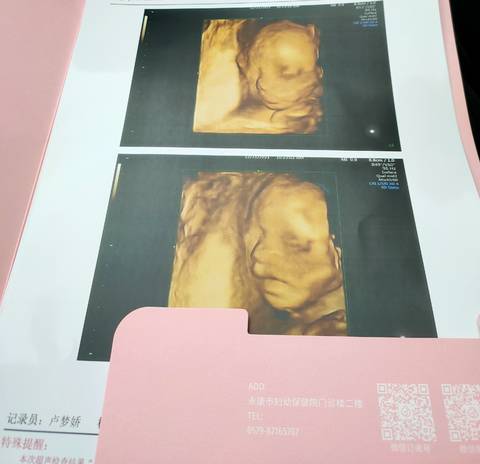

有没有会看四维的姐妹 帮我看看是男宝宝还是女宝宝 是不是大长腿

journal_insert_pic_1688346643journal_insert_pic_1688346652

你好,对于宝宝是男孩女孩虽然很好奇,但是怀孕的单子、数据、表现是判断不出来的,在这也愿你心想事成。

你好。我们是判断不了男宝宝跟女宝宝的,孕期定期检查,我觉得宝宝健康就好的。祝心想事成 。

你好亲爱的,通过这个来判断男孩女孩是不太准确的哈,我们要给他同等的关爱和呵护,也祝你可以如愿以偿,心想事成。

你好,我们都是一样觉得好奇,确实没什么依据,就个惊喜给自己吧,一切顺利!

看不出来,这个单上的数据是很难直接判断男孩还是女孩的哦,其实只要孩子健健康康就好,生下来才最准